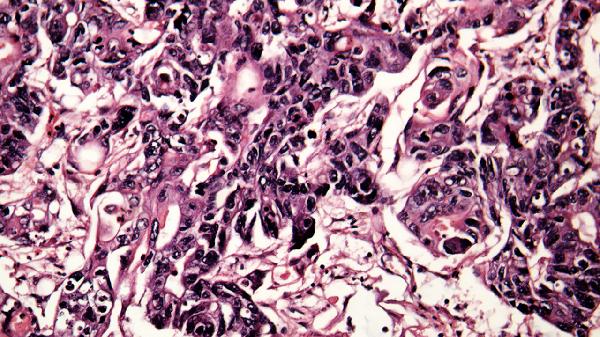

4、皮肤瘀点瘀斑

细菌破坏血管内皮细胞,引发凝血功能障碍,在四肢或躯干出现针尖样出血点或片状紫癜。脑膜炎奈瑟菌感染时可能伴随颈项强直。需避免碰撞,医生可能选用注射用美罗培南、利奈唑胺葡萄糖注射液治疗。